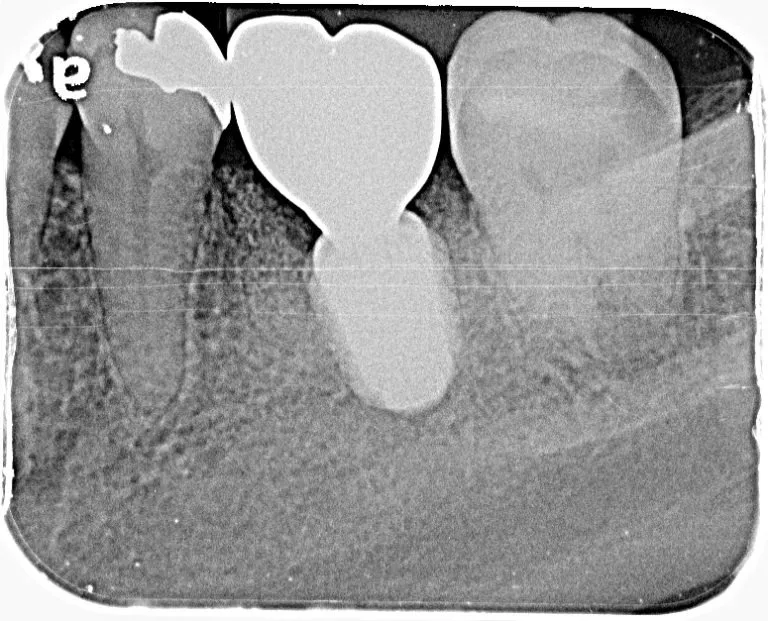

【症例6】

レントゲン写真

治療名

インプラント治療

治療説明

治療期間

約3ヶ月

副作用・リスク

手術中に神経や血管を傷付ける可能性があります。痛み、腫れ、出血がありますまた、インプラントの初期固定が取れない場合、治療期間が長引いたり、すぐに仮歯を装着できない場合があります。

料金

¥495,000(税込)